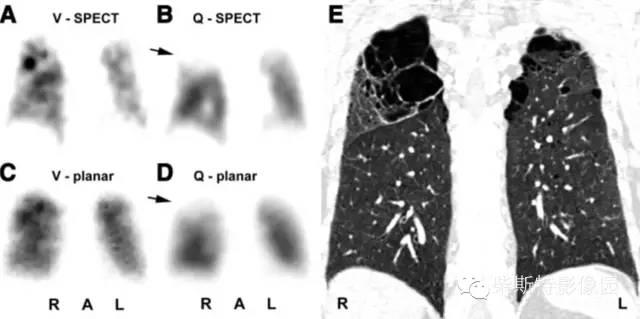

V/Q-SPECT(肺通气/灌注-单光子发射计算机断层成像技术)

V/Q-SPECT显像诊断PE的标准:与平面V/Q显像一样,检测到肺通气与肺灌注不匹配。

coronal-冠状位 sagittal-矢状位 transverse-横断位

几个典型肺栓塞患者的V/Q-SPECT显像:肺通气/灌注不匹配(箭头所指为灌注缺损)

V/Q-SPECT-CT融合显像技术

双肺多发栓塞,节段性V/Q不匹配(SPECT断层现象:A、B),(平面显像:C、D),CTPA:栓子位于右肺中动脉分支和双侧下肺动脉分支